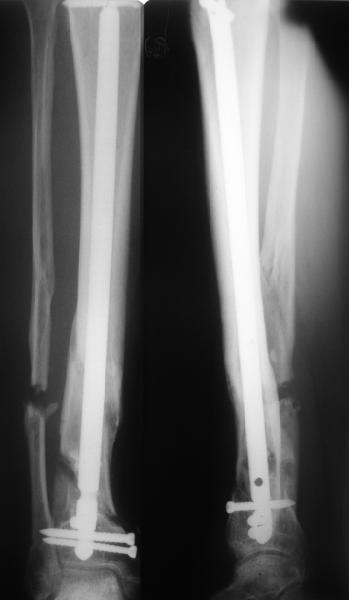

Думаю наиболее оптимальным вариантом будет реостеосинтез стержнем.

Дистальный фрагмент гвоздя, при отсутствии специализированного инструмента АО, можно удалить открыто - выполнить остеотомию передней

стенки.

Учитывая сроки, вполне вероятно, что одномоментно устранить смещение не получится, поэтому может потребоваться 2-х этапное лечение: 1)Удаление гвоздя и ЧКО 2) ЗИО с рассверливанием после восстановления оси и длины.

Гвоздь, конечно же, лучше брать с расширенными возможностями дистального блокирования. Линейка таких гвоздей сейчас представлена довольно широко различными фирмами. У нас в клинике наиболее часто

используется гвоздь MetaDiaFix-T, выпускаемый предприятием ЦИТО. В гвозде дистально раполагается овальное отверстие, в которое очень удачно вводятся два винта и заклиниваются между собой, обеспечивая угловую стабильность. Пример использования такого гвоздя привожу ниже.